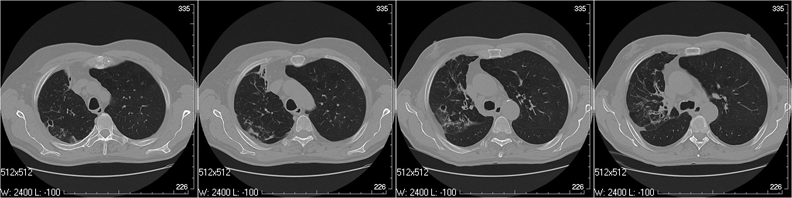

Для достоверной диагностики сложных случаев требуется рентгеновская компьютерная томография (РКТ). Она позволяет получать поперечные сканы (срезы) тела, прилежащие друг к другу, на всем протяжении грудной клетки — от верхушек легких до базальных отделов — без «немых зон». РКТ более достоверно отображает локализацию, характер патологического процесса, его связь с соседними тканями.

За одно исследование получают от 40 до 1 000 отдельных сканов, рентгенолог их оценивает, сравнивает с соседними и впоследствии выполняет мультипланарные реконструкции. Эффективная средняя эквивалентная доза при проведении РКТ — 2,9 мЗв (в зависимости от конституции пациента — от 1,8 до 13 мЗв).

Поствоспалительные изменения в нижней доле правого легкого. Бронхи сближены, просвет неравномерно расширен, стенки фиброзно утолщены. Перибронхиальные фиброзные изменения в легочной ткани, плевральные пластические наслоения.

Изменения в верхней доле — как в нижней. Однако в проекции 3-го сегмента — участок плевроплевмоцирроза с расширенными, деформированными бронхами; полостное образование с фиброзированными стенками. Важно: при столь длительном «туберкулезе» даже при наличии полости деструкции нет характерных очагов и обызвествлений.